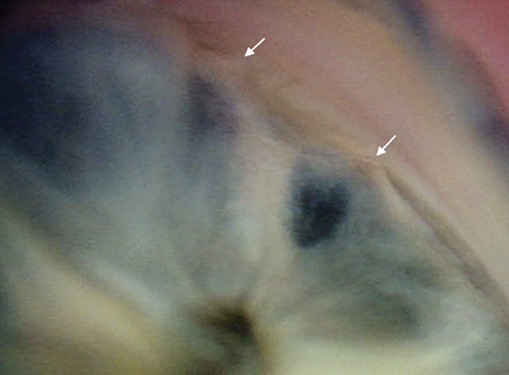

Аналогичные изменения выявлялись и при 3-й степени рубцовой фазы РН — 8 глаз (80 %) (рис. 6). Четвёртая степень характеризовалась в основном дисгенезом УПК — 4 глаза (80 %), в то же время отмечался единичный случай дисгенеза с более грубыми анатомическими изменениями в виде иридокорнеальных сращений, приводящих к уменьшению глубины передней камеры и её деформации (рис. 7), которые преобладали при 5-й, терминальной степени (рис. 8).

Рис. 7. Изображение угла передней камеры глаза ребёнка, 11 лет, с рубцовой ретинопатией 4-й степени, глаукомой (белыми стрелками показана зона иридокорнеального сращения)

Fig. 7. Image of the anterior chamber angle of the eye of an 11 y.o. child with degree 4 cicatrical ROP and glaucoma (white arrow show the area of the iridocorneal adhesion)